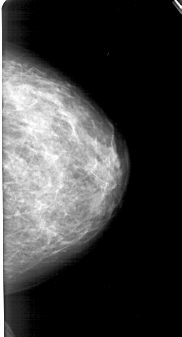

A_1213_1.RIGHT_MLO

RIGHT_MLO LINES 5401 PIXELS_PER_LINE 2596 BITS_PER_PIXEL 12 RESOLUTION 43.5 NON_OVERLAY